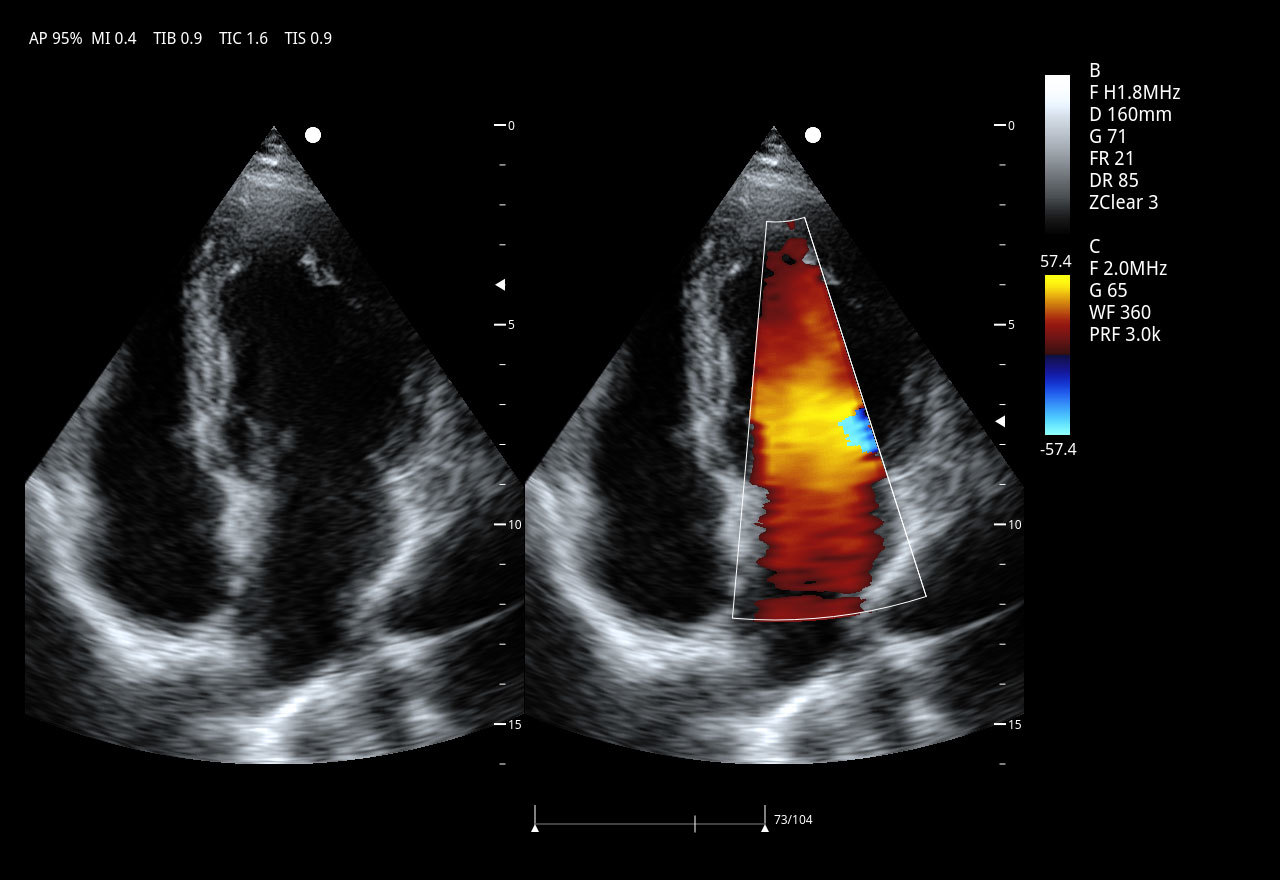

Секторно-фазированный датчик 3P2PA

• Рабочая полоса частот: 1,0–6,5 МГц

• Количество элементов: 64

• Применение: кардиология взрослых и детей, транскраниальные исследования (TCI), абдоминальные исследования.

3. Исследование структуры и функции сердца (эхокардиография)